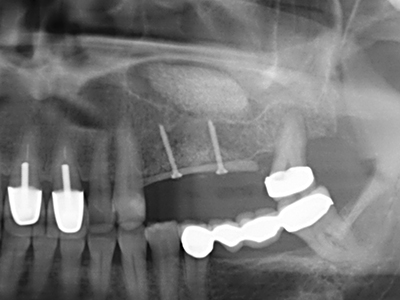

Fig. 11: El ortopantomograma posoperatorio presenta el aumento vertical y la elevación del suelo del seno.

Fig. 12: Después de seis meses de cicatrización se muestra una cresta maxilar vital con unas dimensiones suficientes en todas las direcciones.

Fig. 14: Incorporación de cuatro implantes RSX cónicos (Bego Implant Systems, Bremen).

Fig. 15: El control radiológico realizado al cabo de un año muestra una estabilidad del nivel óseo.

Fig. 16: También condiciones intraorales estables con incorporación de los implantes en la encía queratinizada.